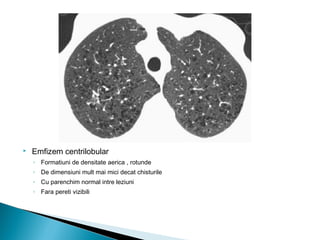

 Emfizem centrilobular

◦ Formatiuni de densitate aerica , rotunde

◦ De dimensiuni mult mai mici decat chisturile

◦ Cu parenchim normal intre leziuni

◦ Fara pereti vizibili